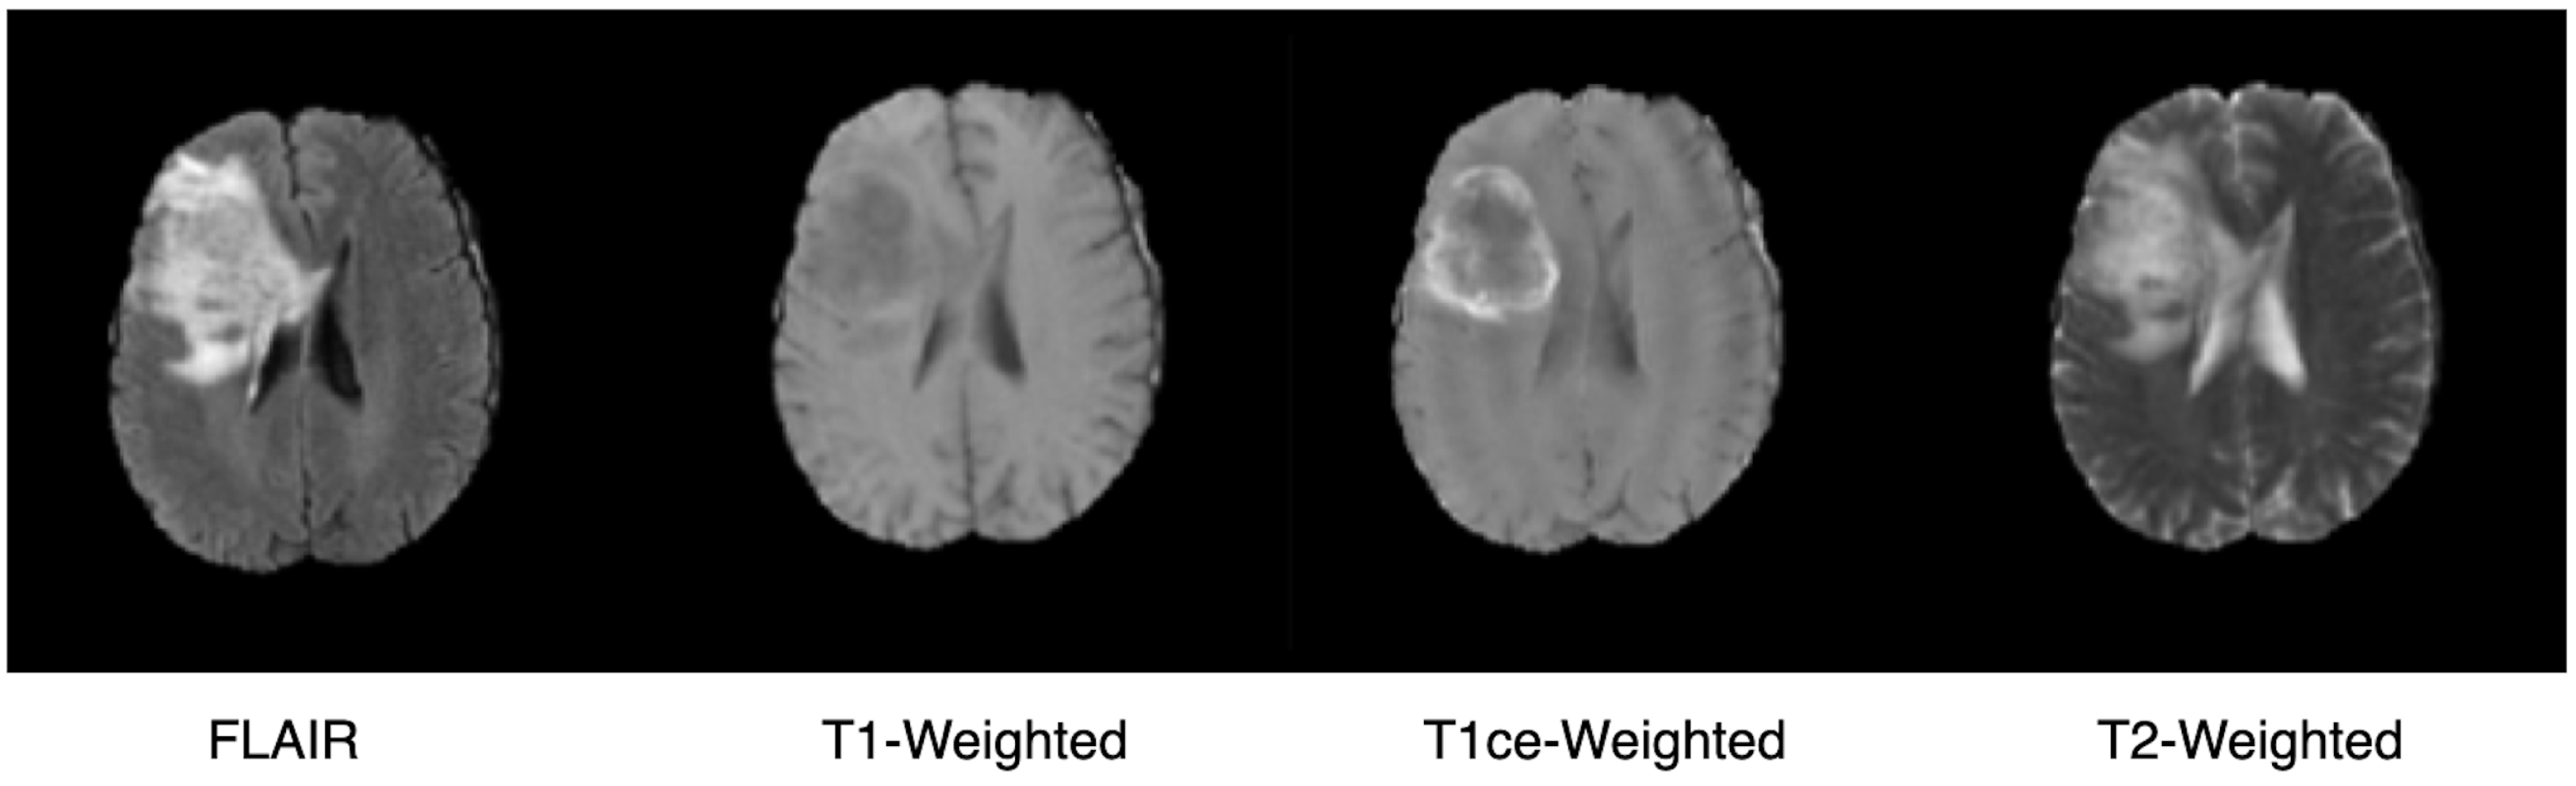

3.2. Dataset

3.3. Segmentation